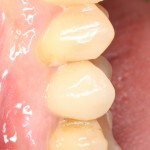

А еще через 2,5-3 месяца можно приступать к протезированию. Мой коллега Макаров Артур сделал временную коронку:

Временная коронка изготавливается из обычной пластмассы, поэтому с цветом особо не заморачиваются. Гораздо важнее состояние десны вокруг коронки (имхо, почти идеально) и ее функционал. Коллега-пациент говорит, что уже забыл, что этот зуб когда-то удаляли.